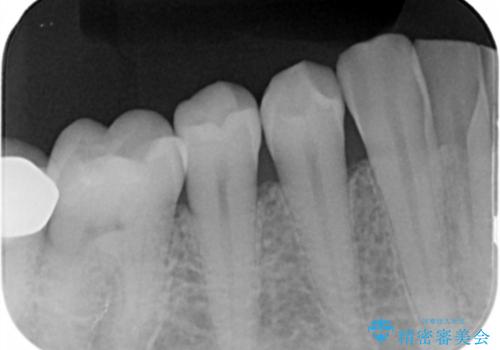

- 右下4番の虫歯治療を希望され来院された患者様です。

セラミックでの治療を希望されたため、切削量・形態を考慮しセラミックインレーでの治療を計画しました。

う蝕を除去した後、CRで裏層した上で形成、印象をしています。

装着時にはラバーダムを使用しています。